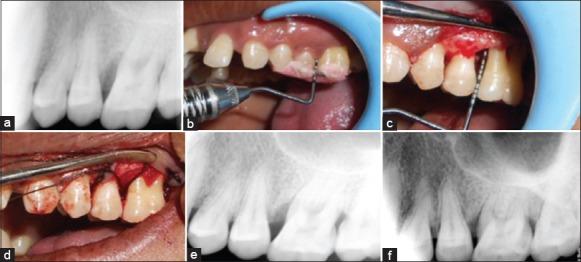

In 10 patients with chronic periodontitis, 20 bilateral infrabony defects were treated with freeze dried bone allograft (FDBA-Group A) and decalcified freeze dried bone allograft (DFDBA-Group B). Clinical and radiographic parameters were assessed preoperatively and at 3 months and 6 months postoperatively. Data thus obtained was subjected to statistical analysis.

对10例慢性牙周炎患者的20个双侧骨下袋缺损,分别用冻干同种异体骨(FDBA - A组)和脱钙冻干同种异体骨(DFDBA - B组)进行治疗。术前及术后3个月和6个月评估临床和影像学参数。对所获数据进行统计分析。